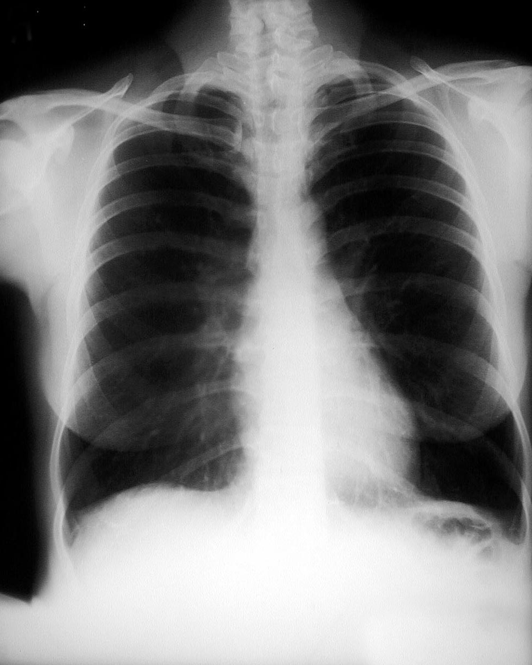

Diaphragm flattening

Diaphragm flattening (increased WOB)